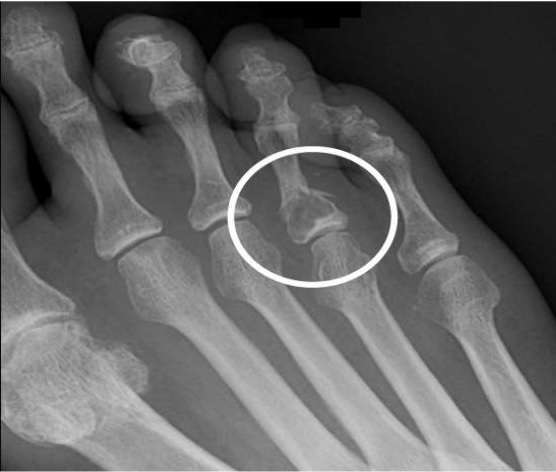

Fibrous Cortical is one of the most common benign lesions or defects found in bones. This defect is caused due to the failure of the nest of fibrous tissue to calcify. Fibrous Cortical defect is also named Non-ossifying fibroma or Non Osteogenic fibroma. This defect is diagnosed accidentally in early childhood. This defect in bones was first described in 1929 by Phemister. Sontag and Pyle gave the radiologic description of this disease in 1941, and its basic and clinical features; also, the natural history of this defect was given by Lichtenstein and Jaffe in 1942.

Fibrous Cortical Defect (FCD), similar to Non-Ossifying Fibroma (NOF), is a benign fibrous tumor in the bones of children and young adults in the cortex of metaphysis. These tumors are typically found in the distal tibia, distal femur, or proximal and, they are rarely found in the upper limb. This defect is usually found in children who lie under the age of 10 years old. Sometimes, it develops into the larger lesion found in young adults and is known as a Non-ossifying fibroma. About 40% of children and adolescents who are skeletally immature may have this defect present in their bones.

Similar to Non-ossifying Fibroma, Fibrous Cortical defect is usually asymptomatic. Many children and adolescents often do not even know that they have this defect present in their bones. This defect is discovered or diagnosed in a child or youngster incidentally through an X-ray for any other purpose. But some people who have experienced this disease reported the following symptoms.

- X-rays help in producing clear and sharp images of bones.